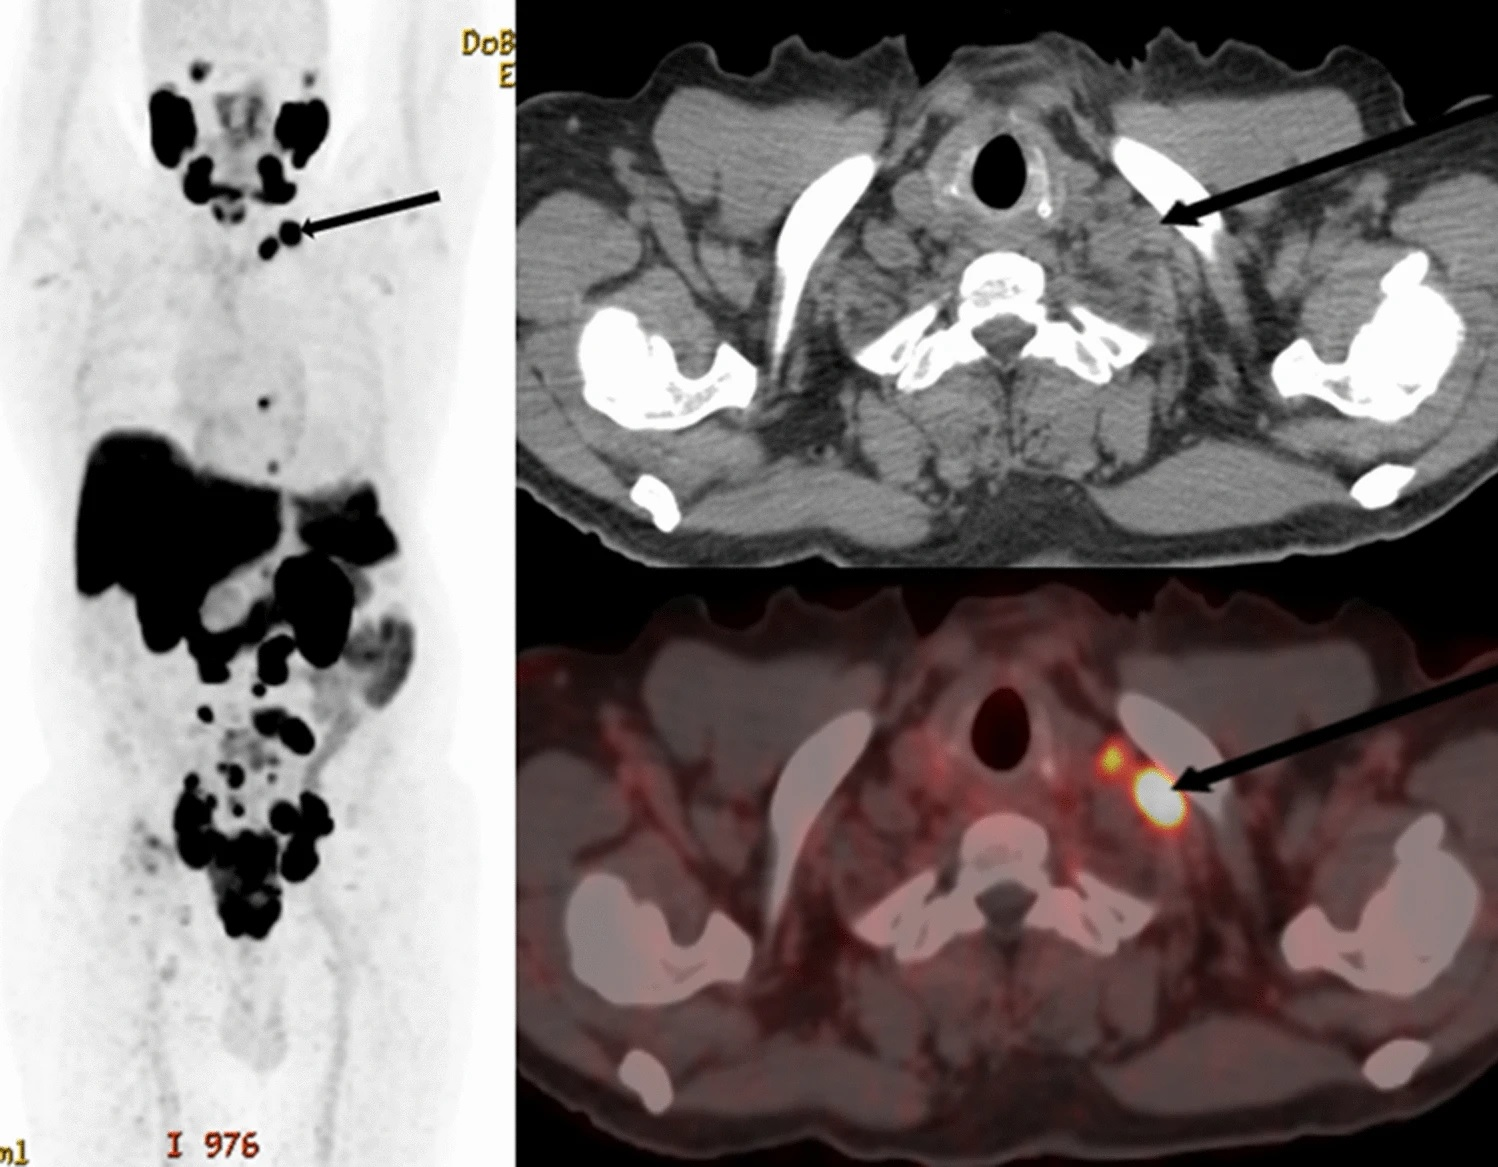

Our most highly-viewed story last week reported on the performance of PET/CT with a new fibroblast activation protein inhibitor (FAPI) imaging agent for detecting bone metastases. In a retrospective analysis of nearly 300 patients, gallium-68 (Ga-68) DOTA-FAPI-04 PET/CT yielded significantly better results than F-18 FDG PET/CT.

- FAPI-PET superior to FDG-PET for detecting bone cancer